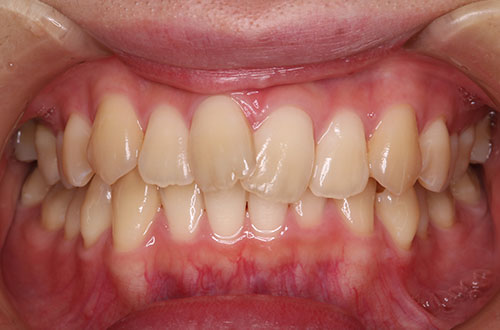

「前歯の部分矯正」~気になる部分だけ治療したい方向け

部分矯正とはその名の通り、「部分的に」歯並びを整える矯正になります。

- 出っ歯を治したい

- すきっ歯を治したい

- 前歯のねじれを治したい などなど

矯正治療とは、金属製のワイヤーやブラケットを用いた矯正装置や、マウスピース型カスタムメイド矯正装置などを歯に装着して、乱れた歯並びや噛み合わせをキレイに改善する治療のことです。凸凹な歯並びや出っ歯、受け口、口元の突出などの噛み合わせの悪い歯並びを治します。